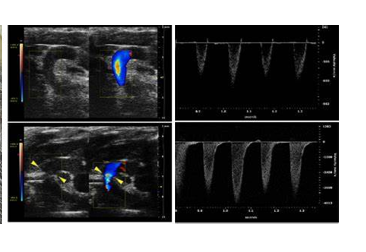

主動脈弓縮窄模型(transverse aortic constriction, TAC)最早由Rockman等于1991年正式建立,是慢性心室肥大常用的疾病模型,用于模擬高血壓或室內壓增高而引起的肥厚性心肌病、心衰。TAC術后,主動脈弓部定量的縮窄引起主動脈血流受阻,左心室壓力負荷增加,誘發了左心室的心室肥厚,早期以向心性肥厚為主,心功能可有效代償,隨著時間的延續,進行性發展為心腔的擴張,最終發展為心力衰竭。

根據動物品系、基因型和手術縮窄程度的不同,心室肥厚和心衰的進程不同。TAC術后1周可發展為顯著性的心室肥厚,2-3周發展為心力衰竭。